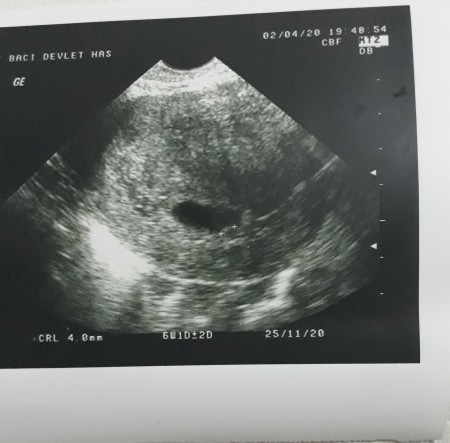

Simdi sukurler olsun 14 haftaligim Rabbim korusun evlatlarimizi sen de bol bol dinlen inşalalh bisey olmaz kesenin fotosunu atsana cnm bak benimki boyleydi bozulmus dedigi kese yani

image